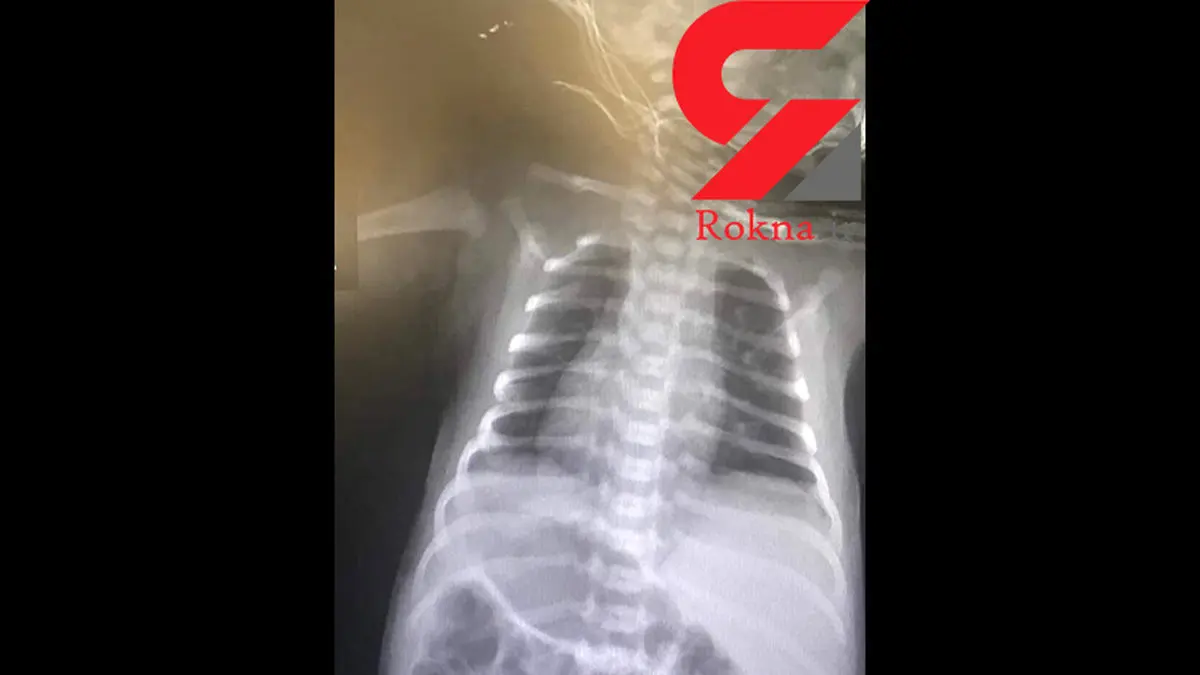

به گزارش رکنا، دکتر فاطمه پورشمسی مسئول مرکز خدمات جامع سلامت گراش و پزشک خانواده این نوزاد گفت: نوزاد پنج روزهای برای معاینات ۵-۳ روزگی به مطب مراجعه کرد که طی انجام معاینات کامل بدن، به قرارگیری نوک قلب در سمت راست شک داشتم و سپس برای اطمینان صد در صد و اطلاع به خانواده، از قفسه سینه و شکم نوزاد عکس تهیه شد که با مشاهده عکس، تشخیص تایید شد.

وی افزود: تولد چنین نوزادانی بسیار نادر است و نوزاد، مبتلا به آنومالی مادر زادی نادری به نام Situs inversus بوده که در آن کلیه احشاء بدن سمت مقابل قرار گرفته یعنی قلب و معده در سمت راست و کبد در سمت چپ قرار دارد که در ۳ تا ۵ درصد از بیماران مشکل قلبی مادرزادی همزمان نیز وجود دارد ولی طی معاینات به عمل آمده نوزاد مشکل خاصی نداشته که برای اقدامات تکمیلی از قبیل اکوکاردیوگرافی ارجاع داده شد. برای ورود به کانال تلگرام ما کلیک کنید.